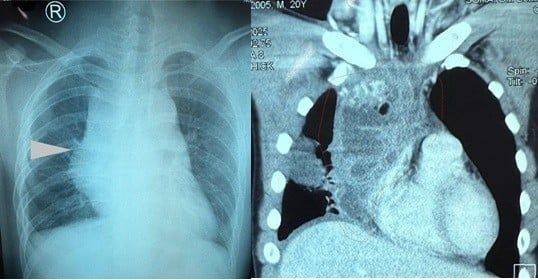

Khoảng 2 tuần trước khi nhập viện người bệnh cảm thấy đau vùng lưng ngay xương vai phải lan ra trước ngực, cảm giác căng tức mệt thở khó được chuyển đến bệnh viện Nhân 115 chụp hình phổi kiểm tra phát hiện u trong lồng ngực với bóng trung thất to.

Kết quả chụp CT ngực có cản quang phát hiện khối u rất to trong lồng ngực chèn ép vào tim, phổi và tĩnh mạch chủ. Kích thước khối U khoảng 10cm X 7cm X 7cm bờ đa cung giới hạn không rõ, đậm độ thấp, thành dày tăng bắt thuốc cản quang, tụ dịch khu trú nhĩ phải, xẹp thụ động thùy dưới phổi (P).

Hầu hết các triệu chứng đều liên quan đến chèn ép các cấu trúc lân cận như đau ngực, khó thở, ho hoặc nhiễm trùng phổi. Chụp X-quang ngực thường cho thấy khối u trung thất trước. CT ngực thường là phương thức chẩn đoán hình ảnh được lựa chọn để chẩn đoán u quái trung thất, giúp xác định vị trí và các cấu trúc lân cận của khối u cũng như các thành phần bên trong gồm mô mềm, mỡ và canxi hóa.